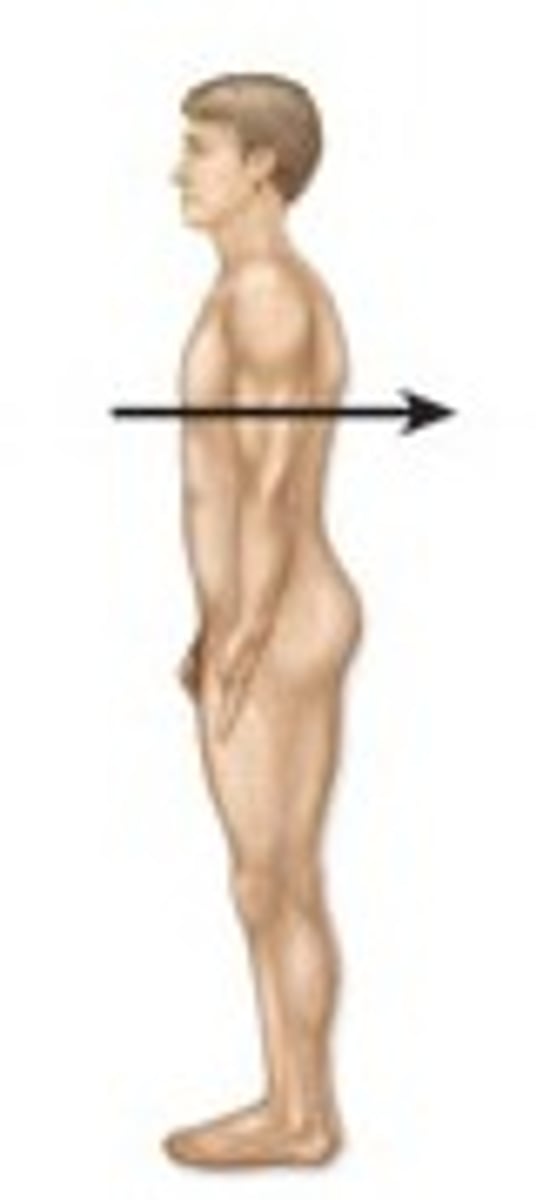

Anterior

Located towards the front of the body

Posterior

Back of the body